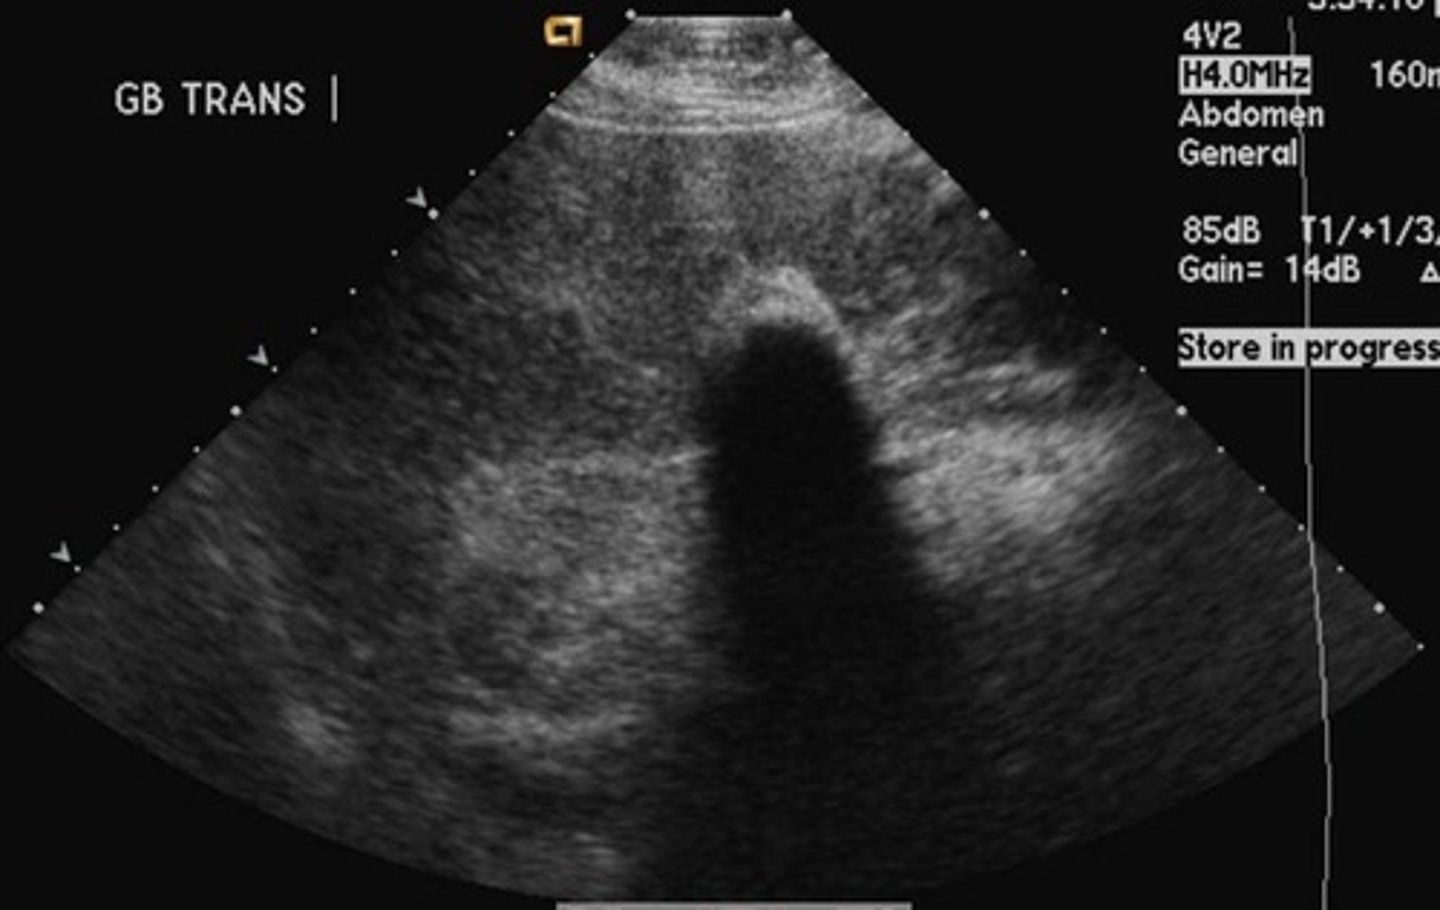

Cholelithiasis sonographic findings

- mobile, echogenic structure within GB lumen that produces posterior shadowing

-WES sign if completely filled with stones

-change in patient position that shows movement

-some stones may adhere to the wall and not cause shadow- twinkle artifact may be used to differentiate b/w a small stone and polyp: